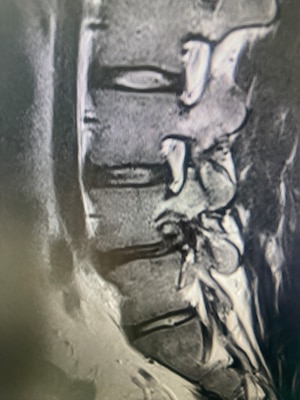

"Uniportal endoscopic spine surgery represents the most minimally invasive technique currently available for treating common spinal conditions such as lumbar disc herniations and foraminal stenosis," Chang explained. "Through a single, small incision, surgeons can access the spine using a high-definition endoscope, minimizing disruption to surrounding muscle, bone, and soft tissue." He said this approach allows for precise decompression of neural elements while preserving normal anatomy.

"One of the greatest advantages of the uniportal technique is its ability to directly target pathology in the foraminal and extraforaminal zones—areas that have traditionally been difficult to access without more invasive exposures," Chang said. "Using a transforaminal or contralateral endoscopic approach, surgeons can visualize and decompress the exiting nerve root along its entire course."